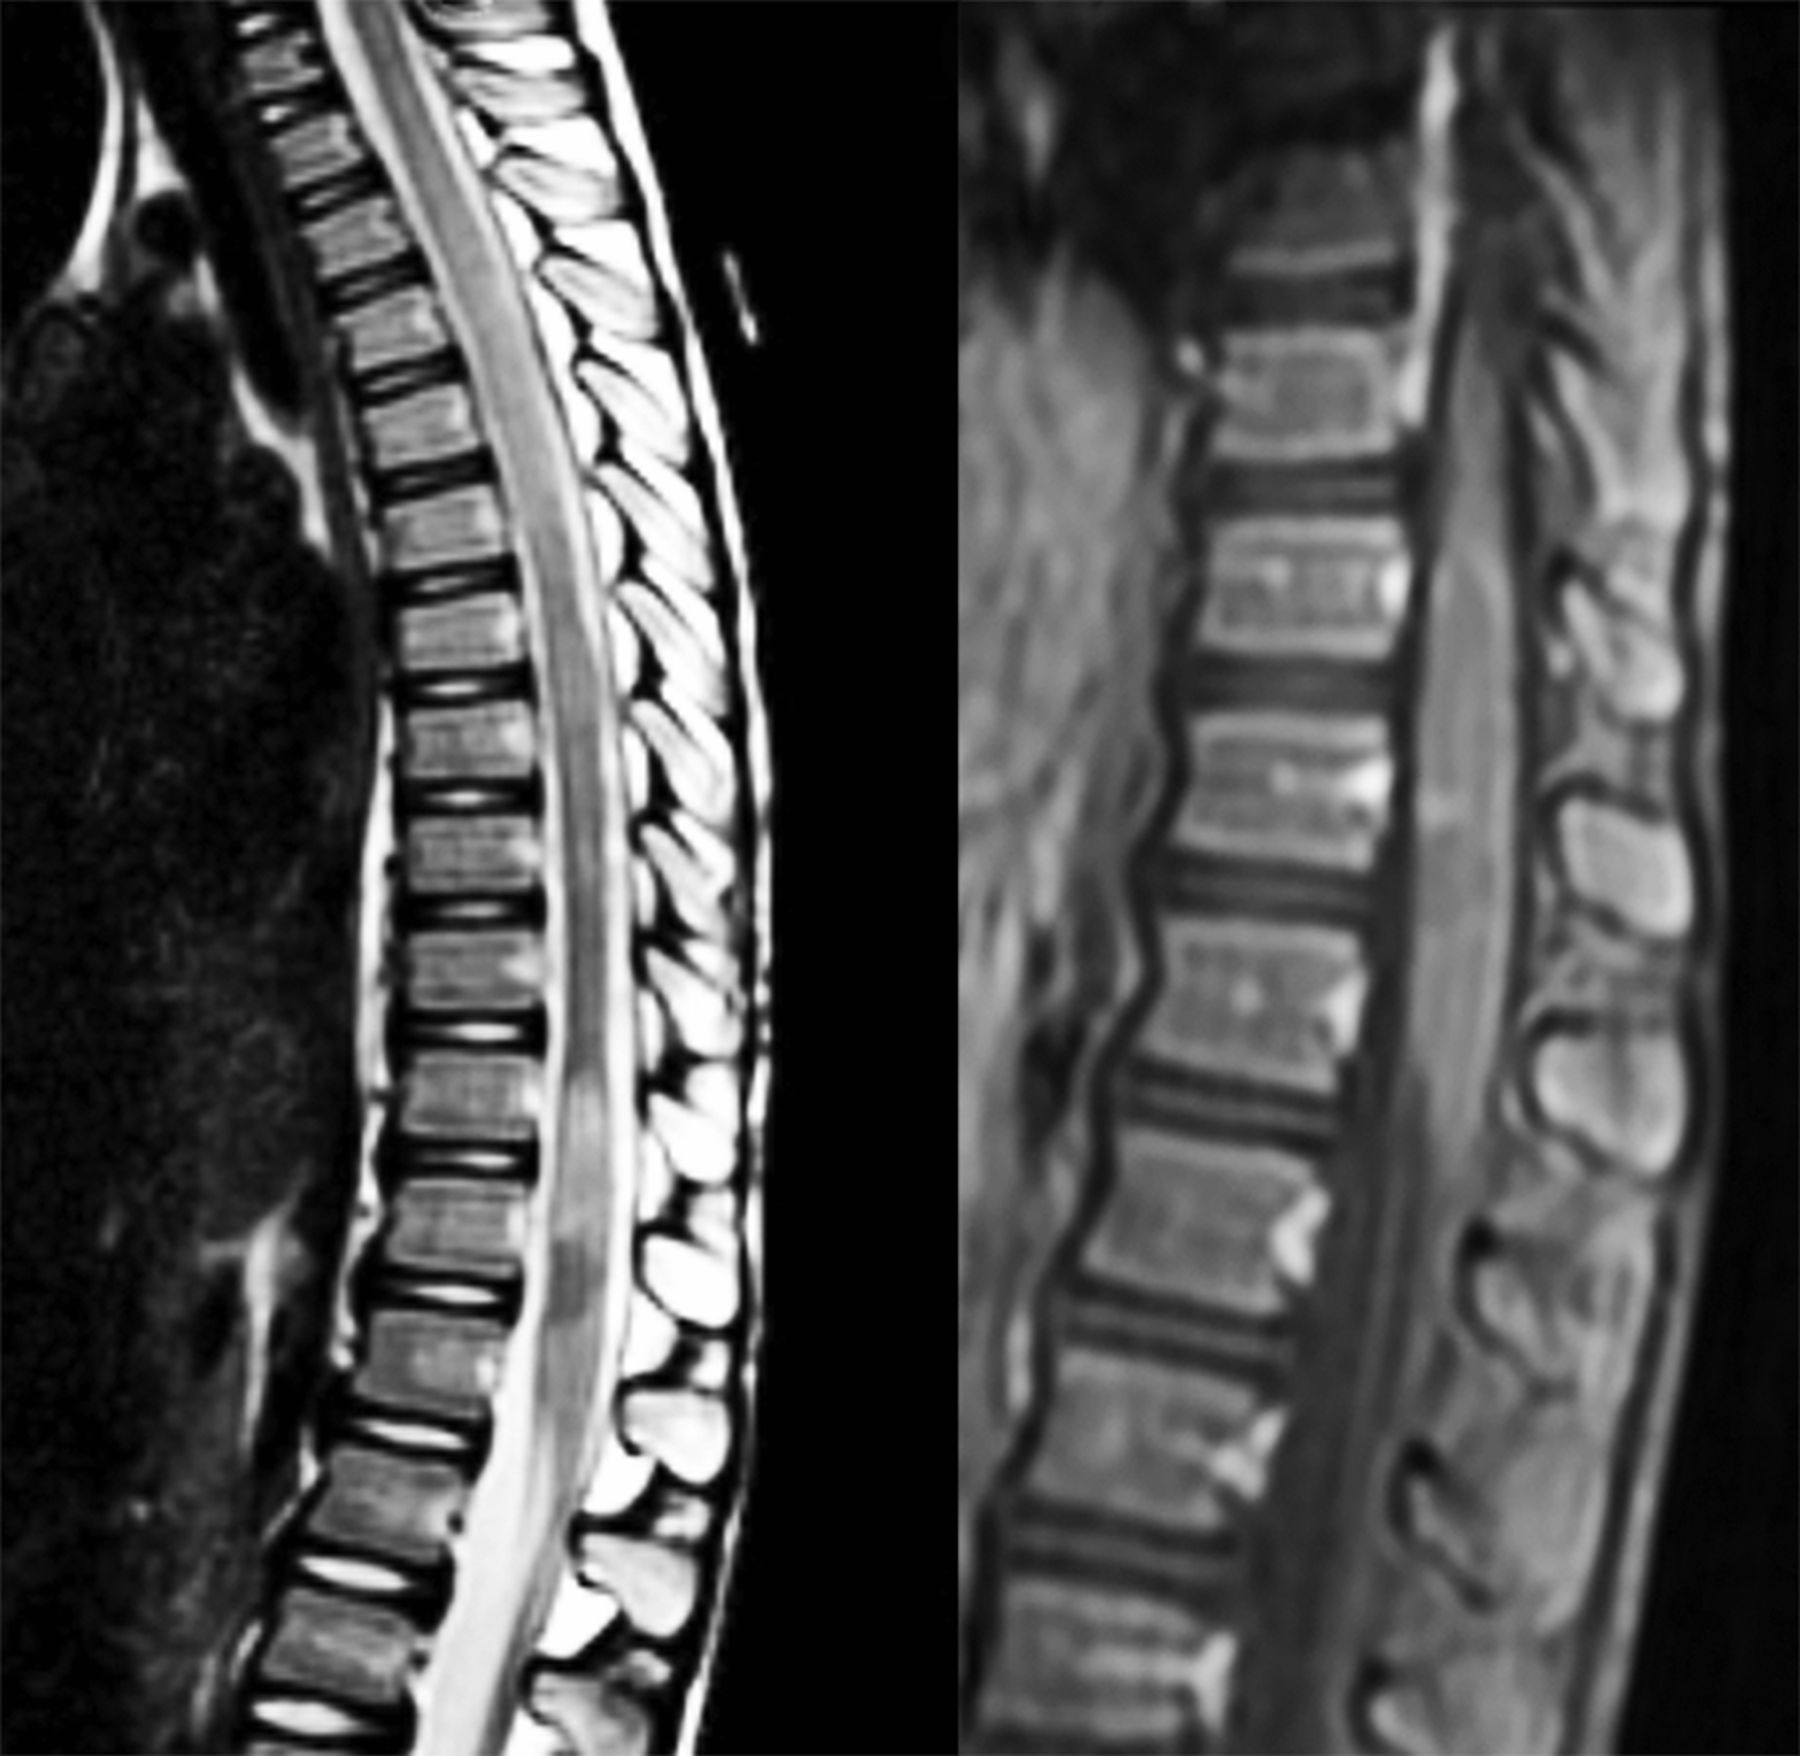

脊髓病变MRI中37.5%(6/16),92.1%(128/139)和71.7%(43/60)的患者MOG抗体,患者AQP4抗体和血清反应阴性的患者,分别为(表3依照表)。病变患者的MOG抗体分布更频繁地在胸腰椎地区(图2)。相比之下,AQP4抗体和血清反应阴性的病人有更多的患者病变分布在颈胸的地区。MOG抗体(6/6)的患者,所有患者血清反应阴性的(43/43)和89.1%(114/128)的患者AQP4抗体损伤覆盖3或更多椎段脊髓MRI矢状。中值(范围)的椎段最长的脊髓损伤患者是6.5 (3 - 14)MOG抗体,AQP4抗体,患者6(-)和4.5(3-19)血清反应阴性的患者(p= 0.3658)。的中央部分的参与脊髓轴向脊髓MRI发现66.7%(4/6)的患者MOG抗体,AQP4抗体,患者的89.8%(115/128)和79.1%(34/43)的血清反应阴性的患者(p= 0.0721)。

图2

图2 复发性纵广泛的横向脊髓炎患者MOG抗体

矢状t2加权MRI脊髓的一个6岁的女孩与复发性纵广泛的横向脊髓炎和髓少突细胞糖蛋白(MOG)抗体(效价1:1,024)显示2纵向广泛的病变。在t1矢状序列,在胸腰椎损伤过渡环对比度增强。